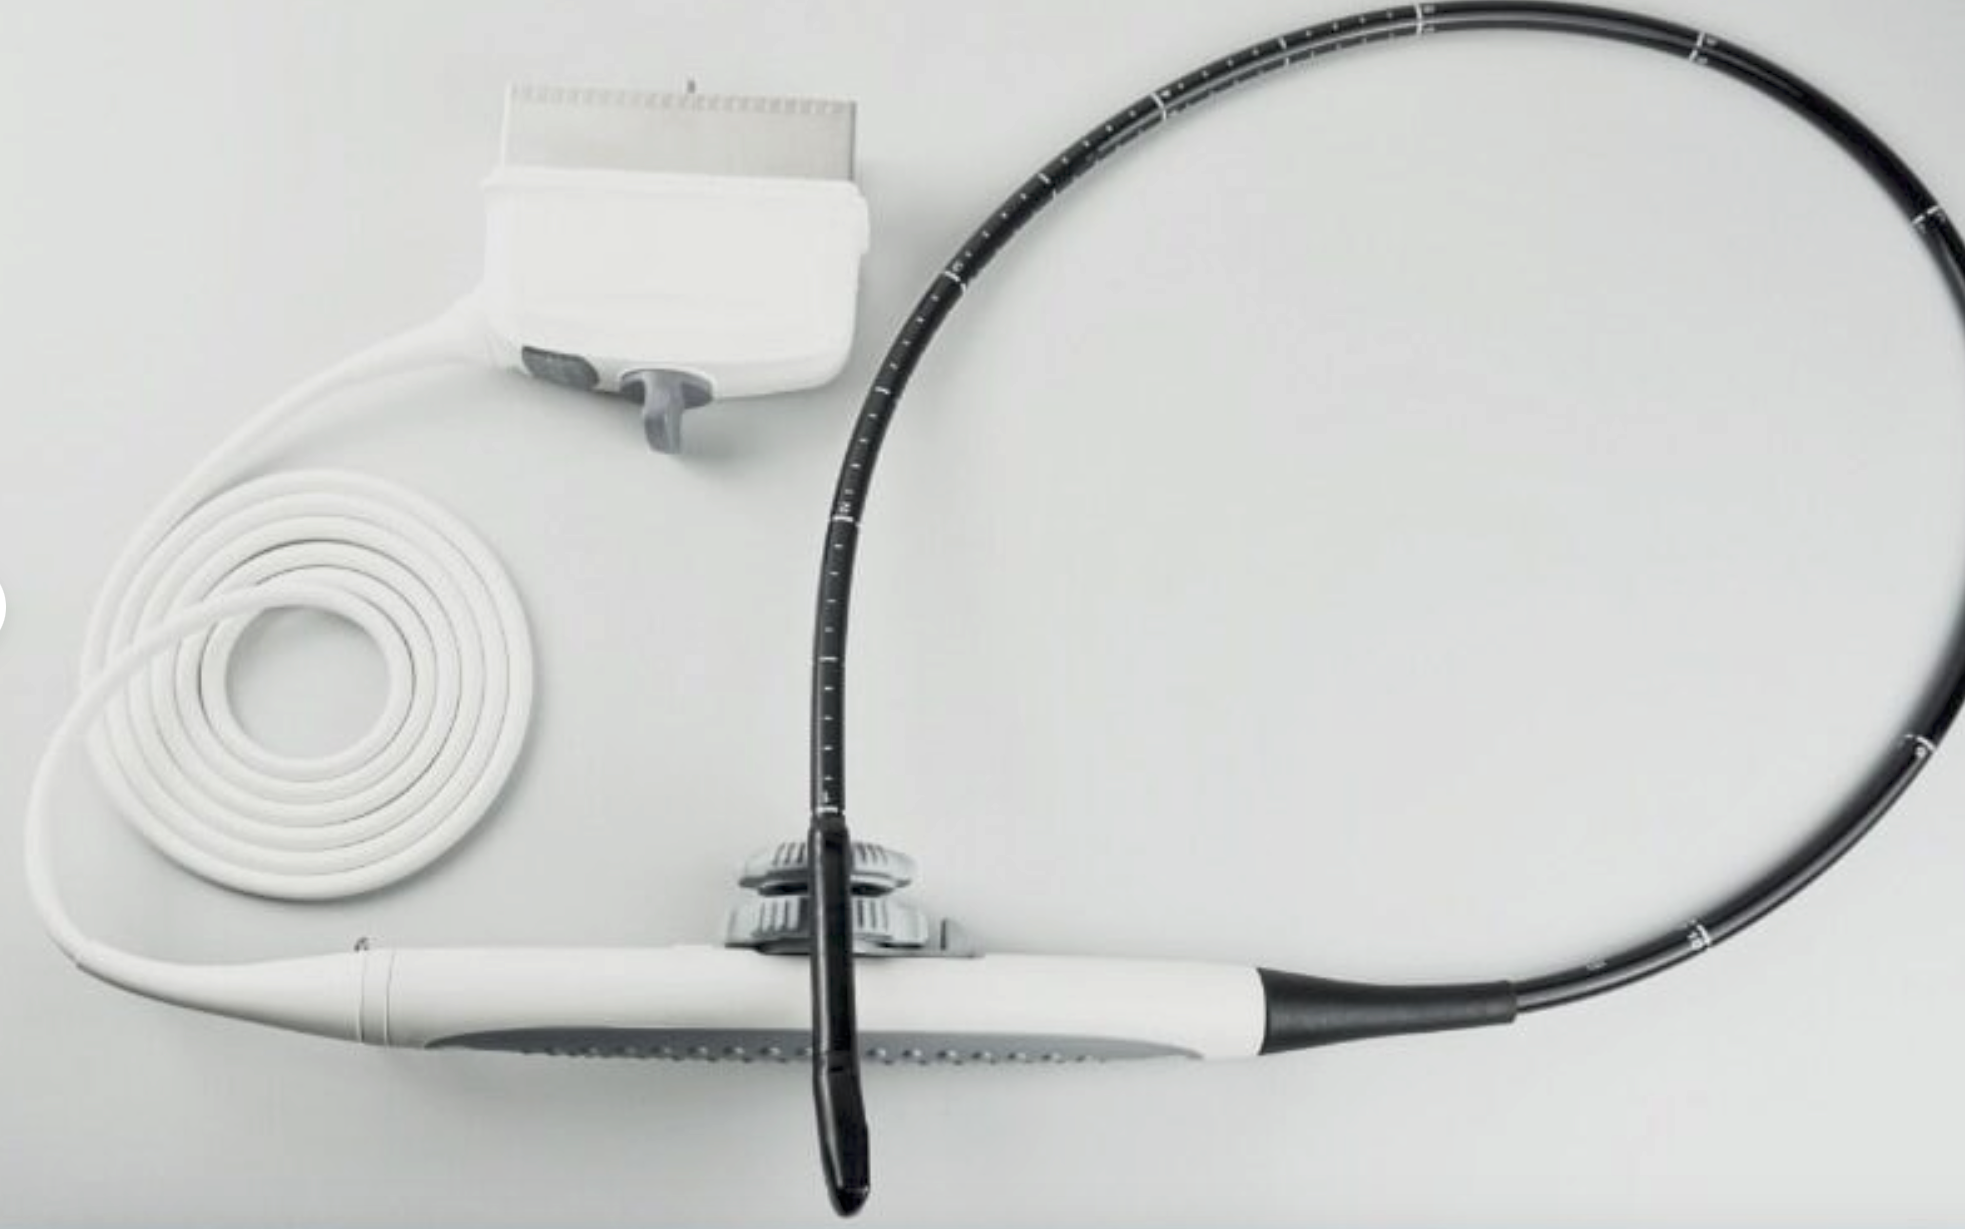

DIAGNOSTIC ULTRASOUND MACHINES FOR SALE

Mindray M9 Portable Ultrasound With 2 Probes

Sale price$ 22,302.88